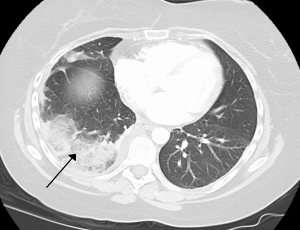

Please note that the CT scan picture above showing a pulmonary infarct (black arrow) is not of my lung, but is rather the pic from the Wikipedia article on Lung Infarction. That article has some gross autopsy photos in it, so if you’re squeamish about such things, consider not clicking the link. Also, some of the first few dates mentioned may seem unimportant, but bear with me because I believe they were.

Luckily, a short while later (which felt like 12 hours) the head ER doctor and the wonderful nurse came in to calmly and rationally explain everything to us. I had massive Deep-Vein Thrombosis (DVT) in my right leg, the clots had separated and lodged in each of my lungs (bilateral pulmonary emboli), each of which causing infarction (tissue death). In short, the pain was due to parts of my lungs dying. Neat. <cough> (ow). Oh, I also had Pleural Effusion when means fluid between my lungs and the tissue that surrounds them because I guess the other stuff wasn’t exciting enough for a Monday morning. We made sure to complain about the previous doctor’s utter lack of compassion and bedside manner, a complaint about which they did not seem surprised.

Word-nerd aside: the scans showed two infarcts. An infarction is the process of tissue death, while an infarct is the actual area of dead tissue caused by blood loss. An infarction is rarely visible on scans unless it happens during something like a PET scan, while an infarct is visible after the fact on CT scans because it’s basically a scar.